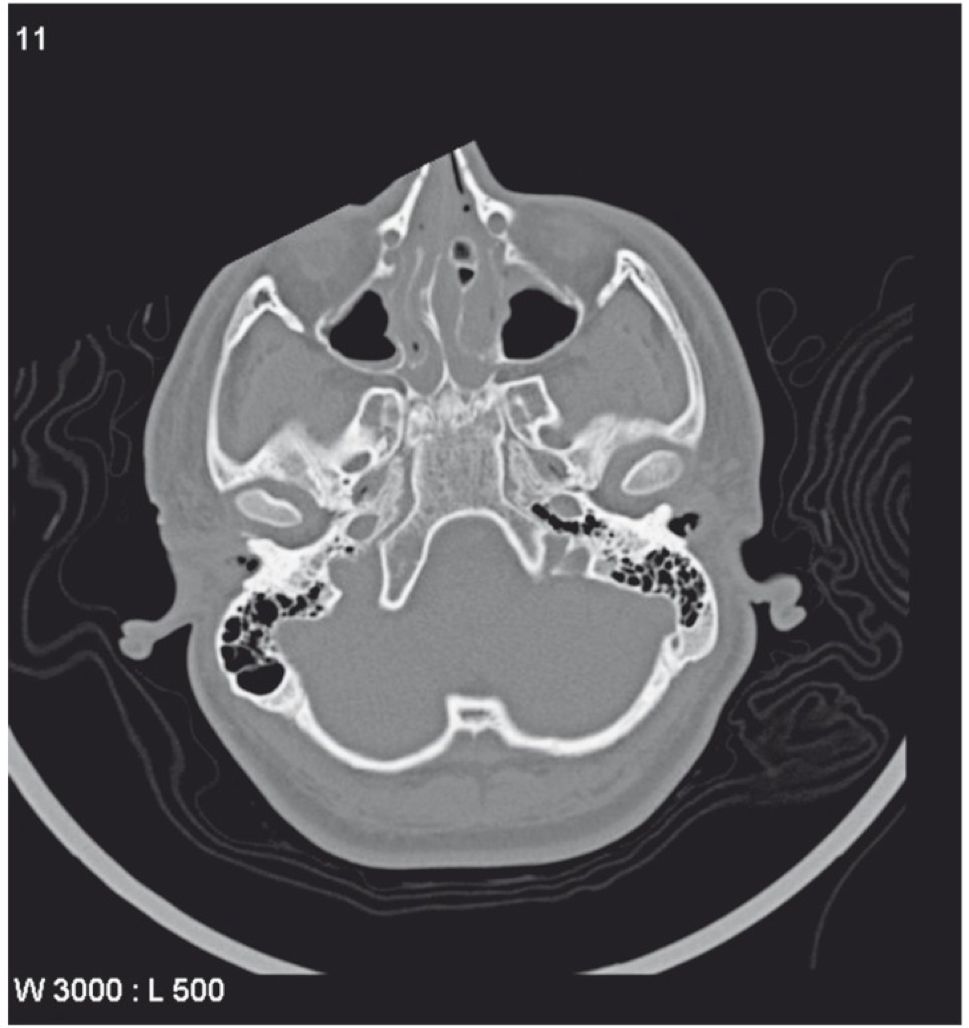

CT示左侧棘孔闭锁(Baltsavias 2012)。

![]()